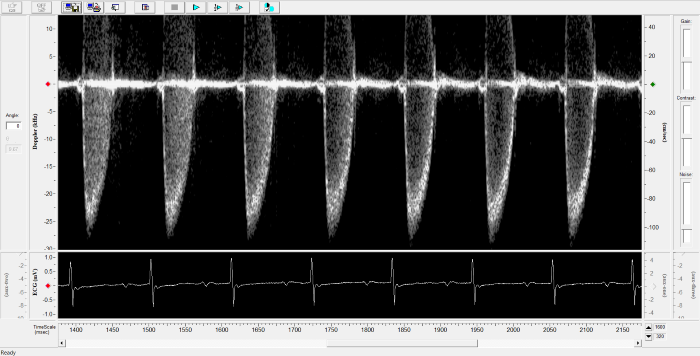

Mouse - Abdominal Aorta

Mouse - Abdominal Aorta. Image Credit: Scintica Instrumentation Inc.